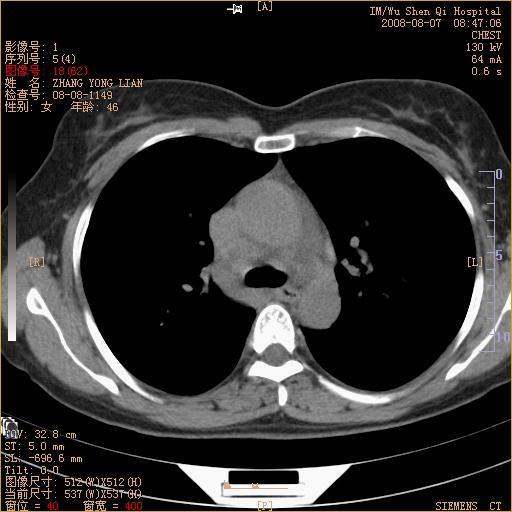

标题: CT15050:女,46岁,咳嗽胸痛一月余 [打印本页]

标题: CT15050:女,46岁,咳嗽胸痛一月余

纵隔窗没发全,左下肺近胸膜处结节。有长毛刺,纵隔淋巴结增大,不排除恶性病变。

考虑肺癌

考虑左肺下叶后基底段周围型肺癌伴纵隔淋巴结转移可能性大。

左下肺ca并纵隔及左肺门区淋巴结转移。

脾脏低密度结节转移不排除。

1)考虑左肺下叶后基底段周围型肺癌伴纵隔淋巴结转移。2)脾内低密度灶,性质待定;不排除转移瘤可能。

考虑左肺下叶后基底段周围型肺癌伴纵隔及肺门淋巴转移。